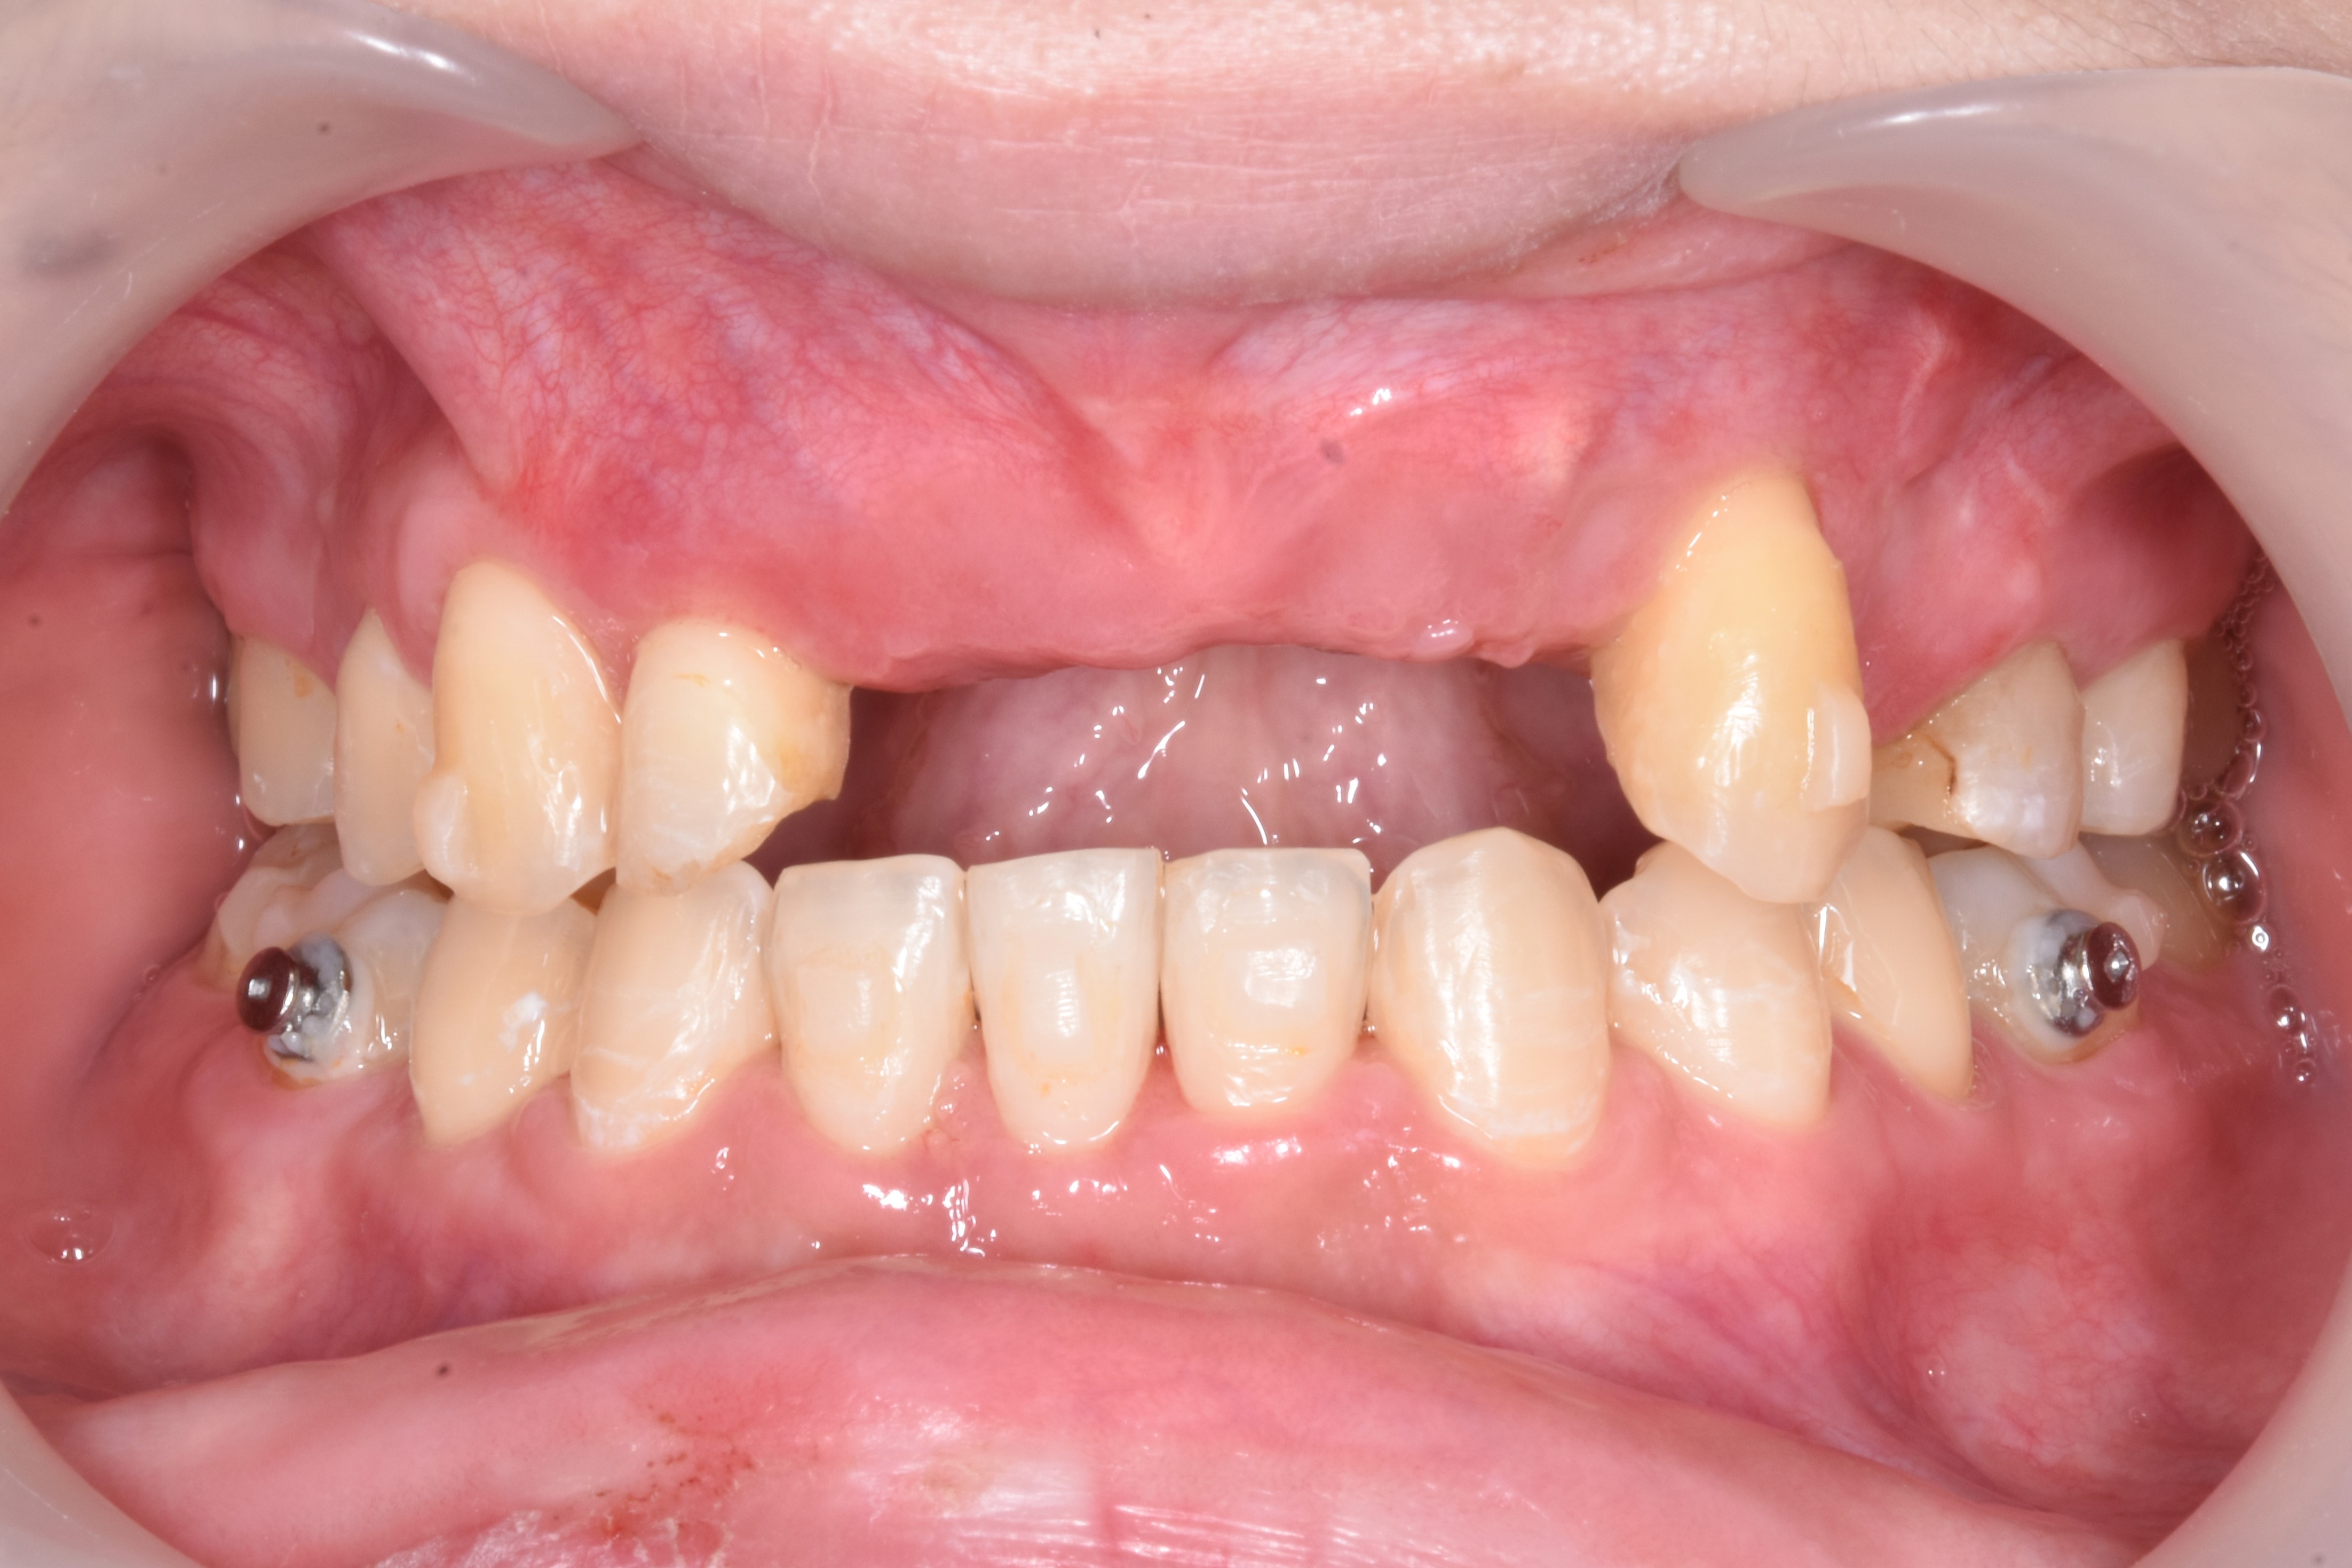

案例五

先把不好的牙根拔除,等待傷口癒合,進行補骨

翻瓣補骨的區域

補入所需骨粉

蓋上可吸收骨膜

*可吸收骨膜:會被身體自然吸收、不需再開刀取出的骨膜,用在補骨手術中,主要功能是隔離軟組織、保護骨粉、協助骨再生

最後縫合傷口,等待癒合